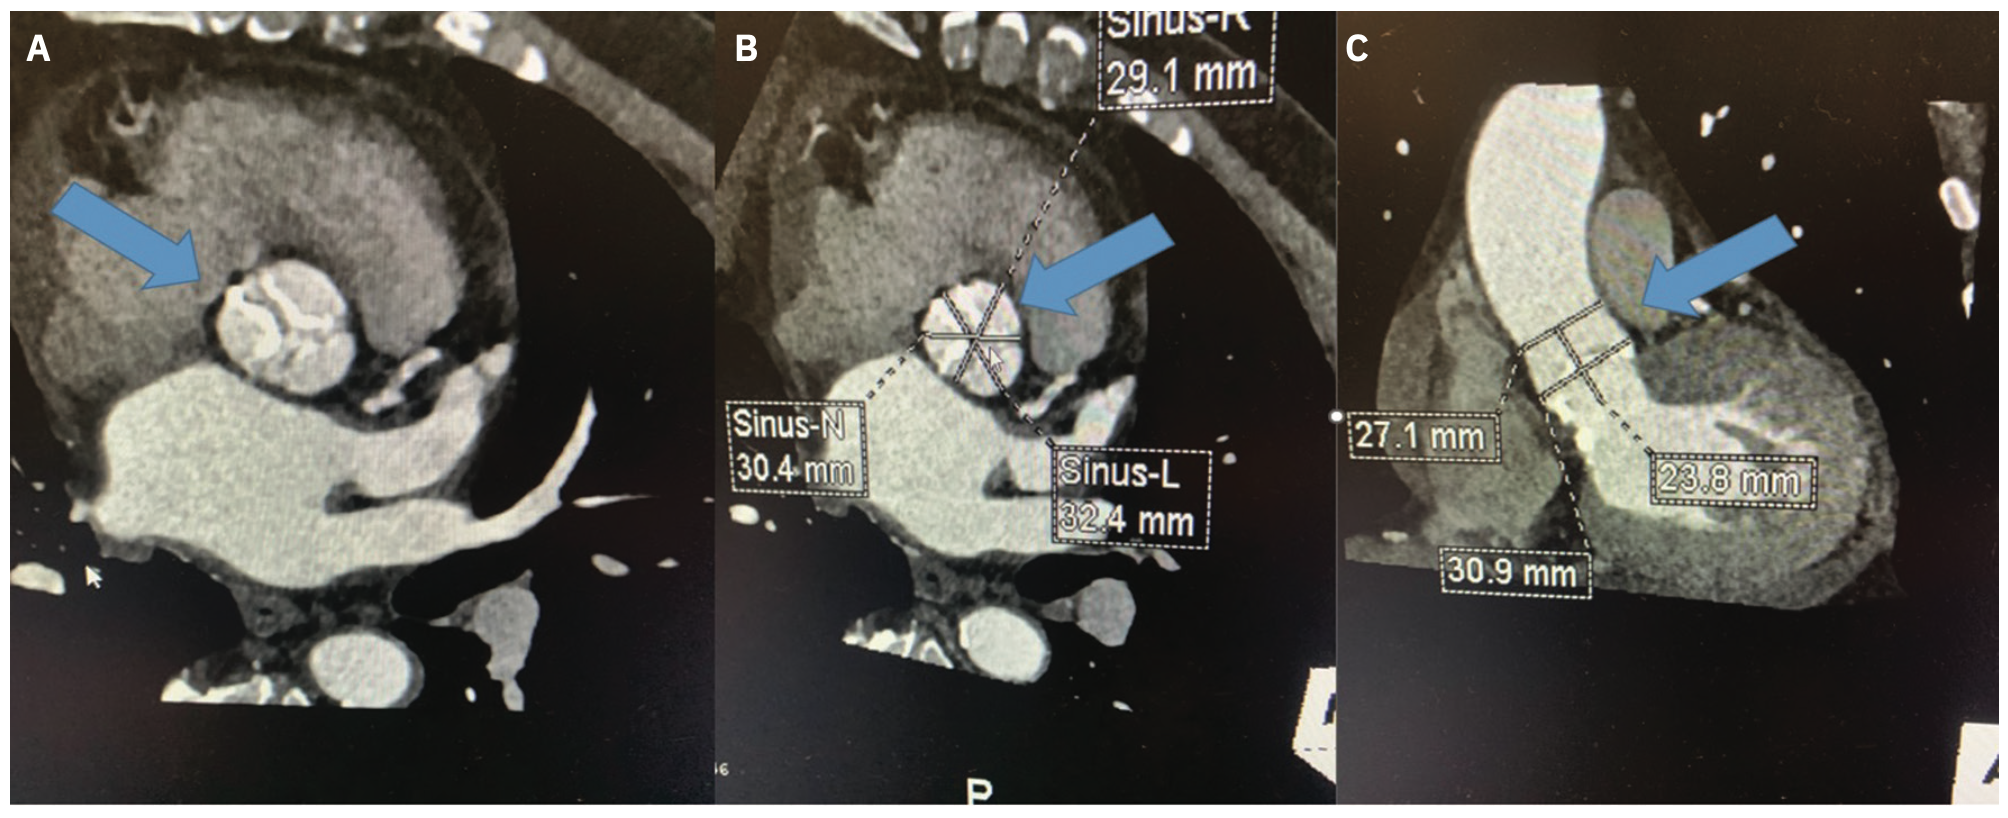

As transcatheter aortic valve replacement has become a frontline treatment for aortic valve stenosis (AS), CT has become the cornerstone imaging modality for the pre-TAVR workup. CT provides 3-dimensional images of the heart, and offers a rapid and complete evaluation of aortic valve morphology and size (Figure 6). CT also evaluates the ascending aorta, coronary arteries, peripheral access vessels, and prognostic factors (Figure 7). Additionally, it provides preprocedural coplanar fluoroscopic angle prediction to obtain complete assessment of the patient. The most relevant dimension in preprocedural planning of TAVR is the aortic annulus, which can determine the choice of prosthesis size.12

Once the location of the aortic root is identified on the unenhanced scan by the CT technologist, the second enhanced scan starts with a 10 mm scan coverage acquired during the initial IV contrast bolus technique, allowing for optimal peak enhancement to the aortic valve. A third scan is initiated, serving as the final portion of the CTA of the chest, abdomen, and pelvis, or whole-body scan. The whole-body CTA evaluates the entire aorta, ilio-femoral arteries, and coronary arteries. The whole-body study guides the physician in obtaining vascular access, as it can visualize the tortuosity of the aorta and the vascular access routes (iliofemoral, subclavian, trans-apical, or direct aorta). CTA is also essential to identify patients with increased anatomical risk for coronary artery occlusion in valve-in-valve (ViV) procedures (Figure 8). CTA is also very useful in the evaluation of late complications, such as perivalvular leaks, thrombosis, and valve displacement.12,13